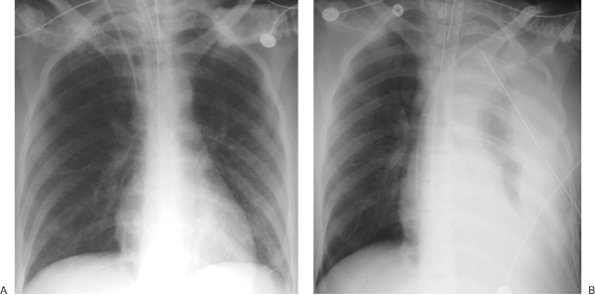

FIGURE 5-6. Malpositioned catheter resulting in ectopic fluid administration. A: PA chest radiograph obtained prior to left catheter placement. The right subclavian central venous catheter tip is positioned over the expected junction of the SVC and right atrium (arrow). B: PA chest radiograph after placement of a new left subclavian central venous catheter shows acute widening of the mediastinum from extravascular placement of the catheter and ectopic infusion of fluid into the mediastinum. The extravascular location of the catheter is not obvious on the radiograph, but the change in mediastinal width should prompt further investigation to confirm catheter position.

FIGURE 5-7. Mediastinal hematoma from subclavian artery perforation. A: PA chest radiograph prior to catheter placement shows a normal upper mediastinal width. B: PA chest radiograph after placement of right subclavian central venous catheter shows acute widening of the mediastinum.